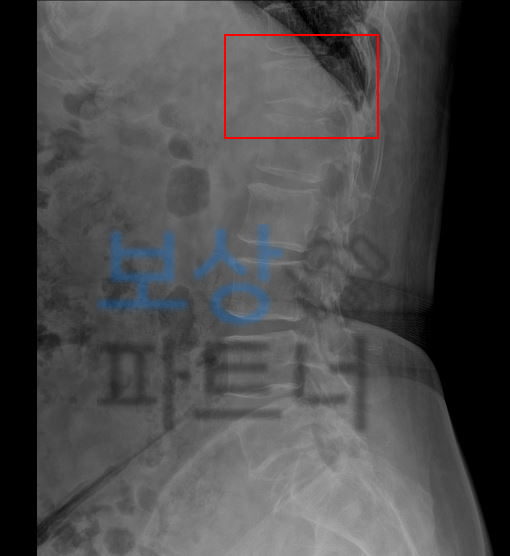

라고 문의해주셨던 김@@님의 실제 보상 사례를 소개해드리겠습니다. 수도권 거주하시는 김@@님께서는 자택에서 발생한 낙상사고로 인해 흉추12번 압박골절 진단을 받으셨습니다.

척추의 골절은 골절 모양의 특성 상 기존 척추의 각도에 영향을 주게 되며

보험 약관에서는 척추 각도의 변형을

장해로 인정하기 때문에 보상받을 수 있는거죠.

보험 약관상 뚜렷한 기형 30%